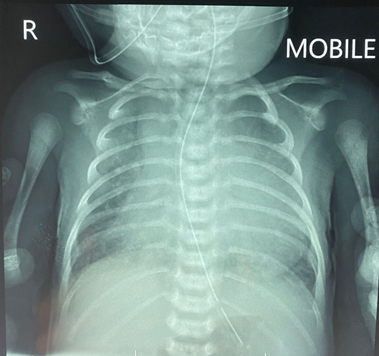

A full-term baby (male, birth weight 3.1 kg) was admitted with signs and symptoms of heart failure, but without cyanosis, at 10 days of life. His pulse oximeter indicated 96% on room air with respiratory rate 56/min, heart rate 147/min, blood pressure 69/35 mmHg. Chest X-ray showed plethoric lung fields and cardiomegaly (Fig. 1). Oxygen was given 1 L/min via a nasal cannula. Frusemide and spironolactone are started. His hemoglobin was 20.0 g/dL, hematocrit 58%, total white blood cells 13,600 µ/L, platelets 181,000 µ/L, CRP 0.1 mg/L, with normal renal function (urea 4.6 mmol/L, Na 133 mmol/L, K 4.5 mmol/L, Cl 95 mmol/L, Ca 2.35 mmol/L). An urgent 2D-Echo showed a large VSD, AP window (Fig. 2) and also PA sling suspected. Thoracic CT angiography confirmed Type 2a PA sling with severe tracheal stenosis. The so-called “tracheal bronchus” gave rise to the right upper lobe; its branching being as if at the usually expected location for the carina. The bifurcation to the right lower lobe and the left lung in this patient was present lower down with abnormal orientation (the bronchi more horizontally oriented than usual). The left PA is located at the T6–7 level just above the carina which resulted in distal airway stenosis (Fig. 3). The SVCs were bilateral structures. Lung volumes appeared fair bilaterally. The coronary arterial origins were normal. Cardiac MRI illustrated the right atrium and the right ventricle dilated, and also reconfirmed PA sling of the left PA as well as AP window between the distal AscAo and the right main PA (Supplementary Movie S1).

Fig. 3 a: CT angiography of axial oblique multiplanar reconstruction (MPR) with maximum intensity projection (MIP) reconstruction showing a large AP window of a distal type (orange arrow) and the abnormally originating left PA (X) causing focal airway stenosis (blue arrow). b: Sagittal MPR image of the distal AP window (orange arrow head). c: Coronal MPR images of the distal AP window (orange arrow). d: Coronal MPR CT angiography with minimum intensity projection (MinIP) reconstruction in lung window showing anatomy of the bronchial tree; the so-called type 2a PA sling causing focal stenosis (blue arrow) at the airway proximal to the origin of the bridging right bronchus to the right lower lobe.